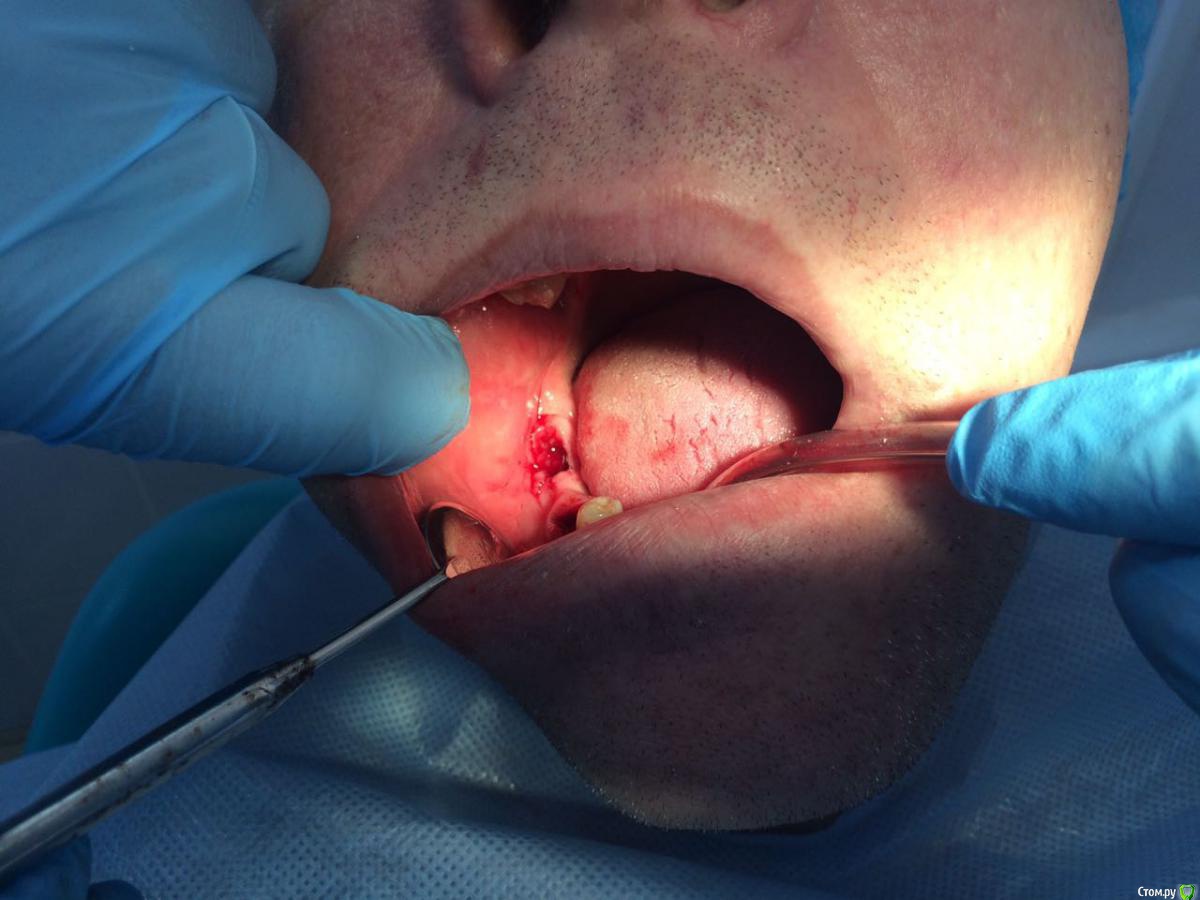

Пациент с жалобами на отсутствие 47 разрушение 46,48. После совещания с ортопедом и терапевтом принято решение удалять 46,48 и устанавливать импланты в позицию 46,47. post-48560-0-74269200-1490419709_thumb.jpgpost-48560-0-43642200-1490419772_thumb.jpgПрисутствует парадонтоз, лечение у пародонтолога прошел заранее. Решено было 46 ставить одномоментно, с графтом и мембранкой, 47 по стандартному протоколу, импланты alpha bio aic 4,2*12, 4,2*10 соответственно. post-48560-0-27512000-1490420040_thumb.jpgpost-48560-0-53003700-1490420066_thumb.jpg Сначала удалил, атравматично с распилом по бифуркации.post-48560-0-43340000-1490420143_thumb.jpgpost-48560-0-35881400-1490420170_thumb.jpgРаскрылся над 47, подготовил ложе, пины параллельности. Здесь вопрос, думаю зря широко отслоился и затронул 46?post-48560-0-32979400-1490420293_thumb.jpgpost-48560-0-94312700-1490420324_thumb.jpgустановка имплантов с фдм, графт в лунки 46 апатос, мембрана Эва. Снять не получилось. Нить моно 5-0. Тут опять вопрос фдм нужно было ставить шире? Но опять же импланты заглубил немного...post-48560-0-50977700-1490420493_thumb.jpg и контрольный. Конструктивная критика приветствуется)))